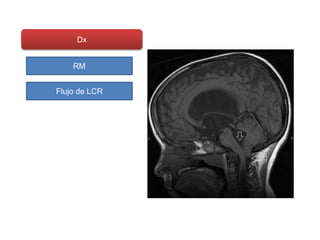

Dx

RM

Flujo de LCR